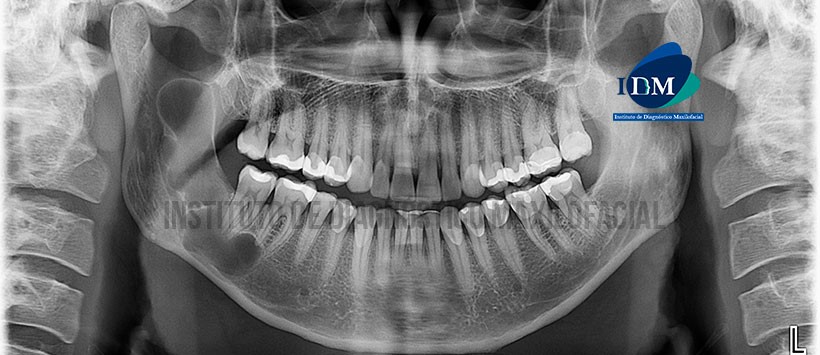

En la radiografía panorámica (Figura 1) se observa una imagen radiolúcida de limites definidos y bordes corticalizados, localizado en cuerpo y rama mandibular derecho.